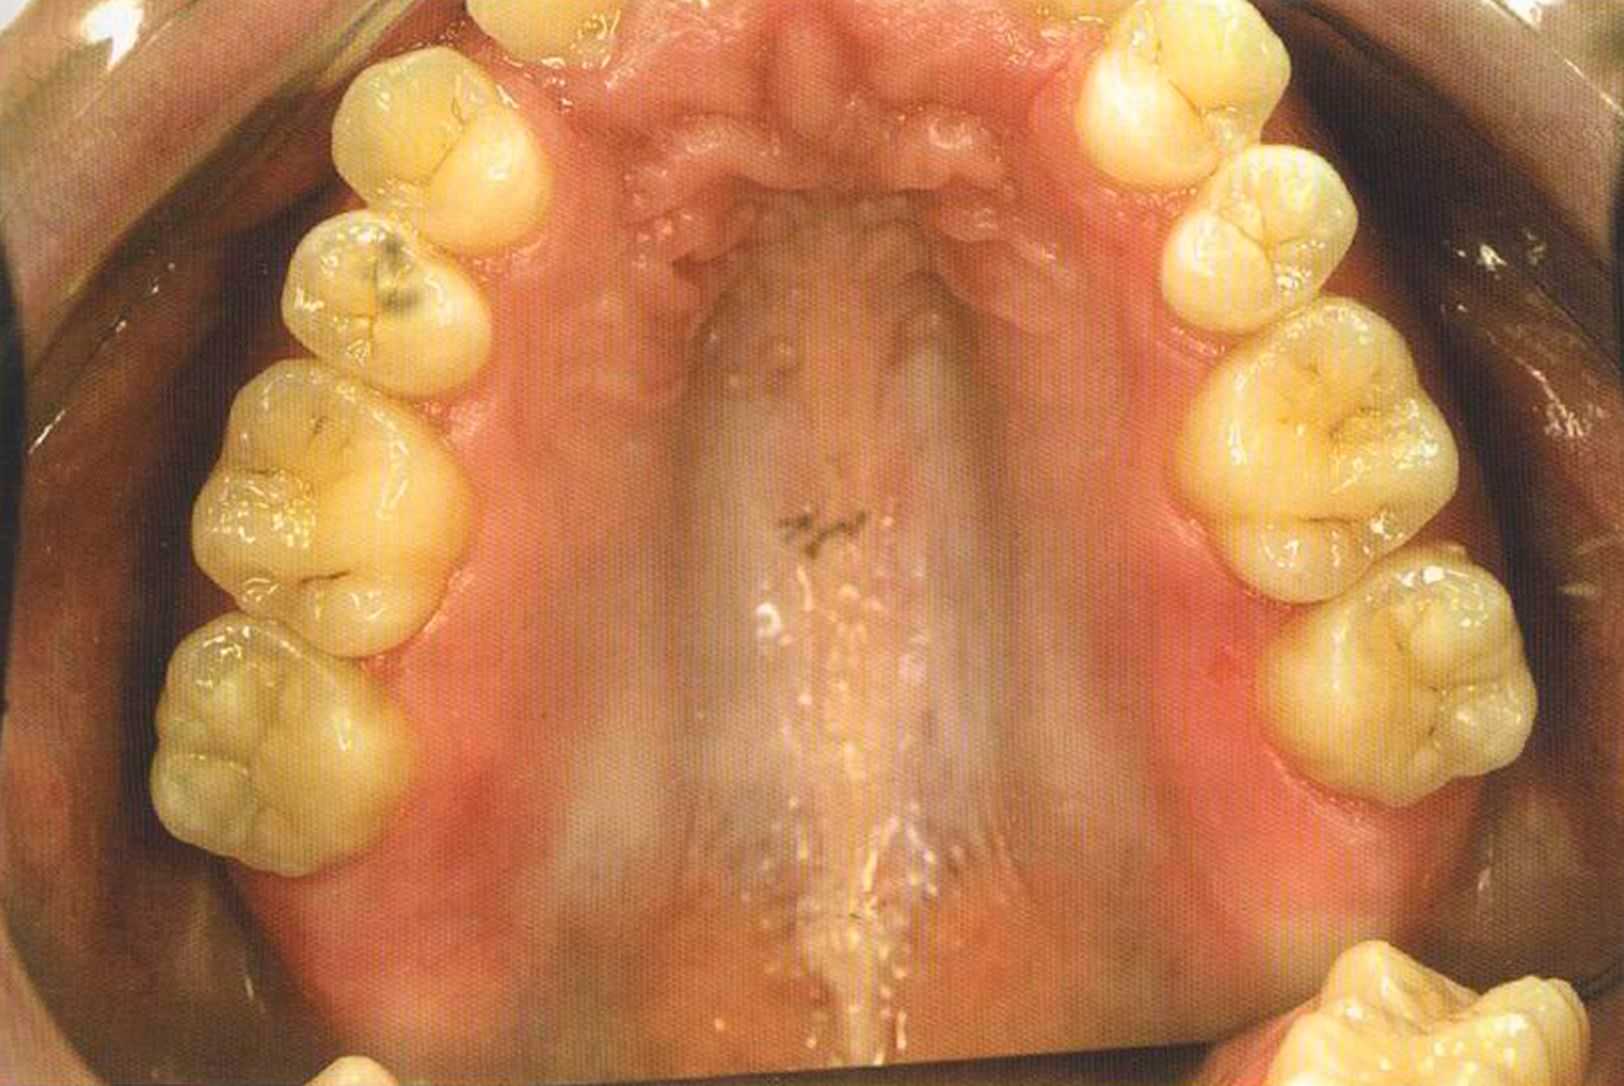

Только что зацементированные коронки. До сих пор сохранилось воспаление десневого сосочка. Уже через несколько дней он будет здоровым, бледно-розового цвета.

Зафиксированные на цемент коронки в полости рта. Видны излишки цемента, которые потом легко удалить, они отскакивают, как яичная скорлупа.